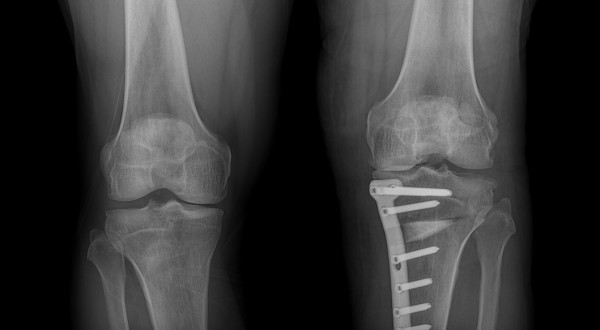

절골수술은 무릎 관절의 비정상적인 정렬을 교정하기 위한 수술적 방법입니다. 이 수술은 주로 관절염으로 인한 통증과 기능 장애를 겪고 있는 환자들에게 시행됩니다. 수술 과정에서는 뼈를 절단하고 재정렬하여 무릎에 가해지는 압력을 분산시킴으로써, 관절에 대한 스트레스를 줄이고 통증을 완화시킵니다. 이러한 접근법은 관절의 수명을 연장시키고, 궁극적으로는 관절 교체 수술을 피할 수 있게 해줍니다.

절골수술과 연골재생 모두 무릎 관절의 통증을 줄이고 기능을 개선할 수 있는 유망한 치료법입니다. 환자는 수술 후 더 활동적인 생활을 할 수 있게 되며, 관절의 건강과 수명이 향상됩니다. 그러나 이러한 접근법은 수술 관련 위험, 장기적인 회복 과정, 그리고 개인별 치료 반응의 차이 등을 고려해야 합니다.